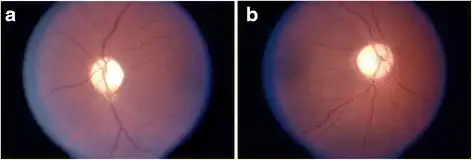

a-e) MRI of the brain demonstrating characteristic findings in DRPLA Optic atrophy on fundoscopic exam in DRPLA. Very pale optic discs are evident bilaterally. a) OS, and b) OD

Optic atrophy on fundoscopic exam in DRPLA. Very pale optic discs are evident bilaterally. a) OS, and b) OD